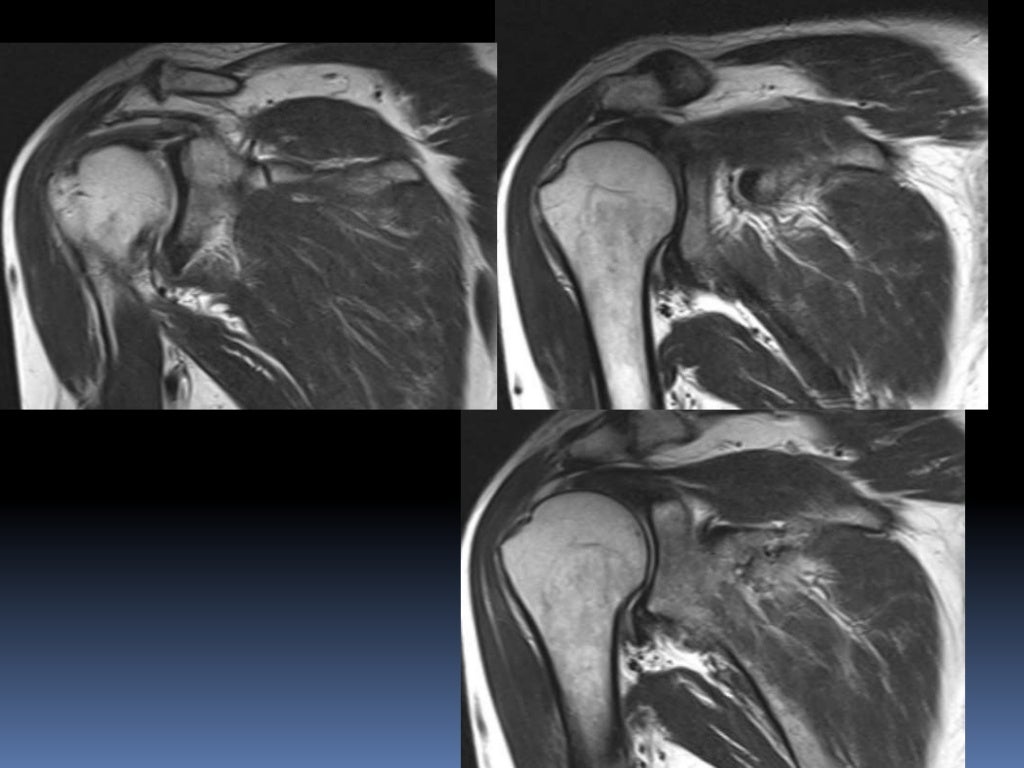

What Is A Shoulder Mri . An mri scan uses magnets and radio waves to capture images of your body’s internal structures. What is a shoulder mri? The mri allows accurate assessment of any pathologic changes of the structures of the shoulder, including the glenoid labrum, the humeral head, the articular. However, the technical jargon in mri reports. What is a shoulder mri scan? Mri of the shoulder is a powerful tool to non invasively diagnose abnormalities of the shoulder. Magnetic resonance imaging (mri) is a critical diagnostic tool used to assess shoulder injuries and conditions. Mri of the shoulder provides detailed images of structures within the shoulder joint, including bones, tendons,. A shoulder mri scan makes it possible to assess not only the condition of the rotator cuff tendons, but also other potential sources of problems,. What is mri of the shoulder?

What is a shoulder mri? A shoulder mri scan makes it possible to assess not only the condition of the rotator cuff tendons, but also other potential sources of problems,. What is mri of the shoulder? Magnetic resonance imaging (mri) is a critical diagnostic tool used to assess shoulder injuries and conditions. An mri scan uses magnets and radio waves to capture images of your body’s internal structures. The mri allows accurate assessment of any pathologic changes of the structures of the shoulder, including the glenoid labrum, the humeral head, the articular. Mri of the shoulder provides detailed images of structures within the shoulder joint, including bones, tendons,. Mri of the shoulder is a powerful tool to non invasively diagnose abnormalities of the shoulder. However, the technical jargon in mri reports. What is a shoulder mri scan?

What Is A Shoulder Mri Mri of the shoulder provides detailed images of structures within the shoulder joint, including bones, tendons,. Mri of the shoulder provides detailed images of structures within the shoulder joint, including bones, tendons,. A shoulder mri scan makes it possible to assess not only the condition of the rotator cuff tendons, but also other potential sources of problems,. What is a shoulder mri? However, the technical jargon in mri reports. What is a shoulder mri scan? What is mri of the shoulder? The mri allows accurate assessment of any pathologic changes of the structures of the shoulder, including the glenoid labrum, the humeral head, the articular. Mri of the shoulder is a powerful tool to non invasively diagnose abnormalities of the shoulder. An mri scan uses magnets and radio waves to capture images of your body’s internal structures. Magnetic resonance imaging (mri) is a critical diagnostic tool used to assess shoulder injuries and conditions.

MRI AP shoulder. Unidad Especializada en Ortopedia y Traumatologia en What Is A Shoulder Mri Mri of the shoulder provides detailed images of structures within the shoulder joint, including bones, tendons,. Magnetic resonance imaging (mri) is a critical diagnostic tool used to assess shoulder injuries and conditions. The mri allows accurate assessment of any pathologic changes of the structures of the shoulder, including the glenoid labrum, the humeral head, the articular. However, the technical jargon. What Is A Shoulder Mri.

MRI Shoulder How we do it How is MRI Shoulder done at Mater Dei Hospital What Is A Shoulder Mri What is mri of the shoulder? The mri allows accurate assessment of any pathologic changes of the structures of the shoulder, including the glenoid labrum, the humeral head, the articular. Mri of the shoulder is a powerful tool to non invasively diagnose abnormalities of the shoulder. Mri of the shoulder provides detailed images of structures within the shoulder joint, including. What Is A Shoulder Mri.